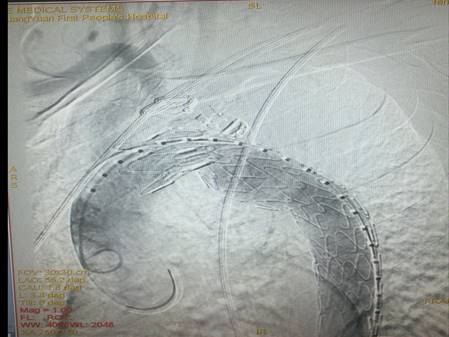

患者的病情就是命令,在紧急情况之下,为保患者生命无忧,心胸外科副主任母存富立即协调相关科室,由血管外科硕士王贤芝医师、心胸外科团队成员在局麻、DSA造影下行“胸主动脉夹层动脉瘤腔内修复术”,参与此次手术的还有麻醉科王义主任、王莉副主任医师,心内科胡永奎副主任医师,介入科李江涛主任、杨华护士长等医护人员。手术过程十分顺利,造影提示瘤体完全封闭、支架无内漏,股动脉穿刺点无渗血。术后患者生命体征平稳,病情恢复良好。